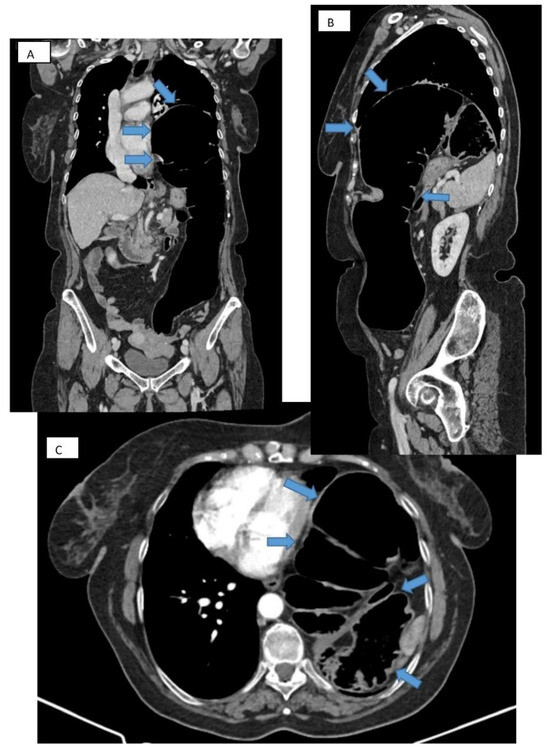

Computed tomography refines the diagnosis by accurately identifying the location, dimensions of the defect, the hernial sac, and the intrathoracic herniation of viscera [17] (Figure 3A–C). Tomographic imaging represents a key element in establishing therapeutic decisions. CT has a sensitivity for left-sided injuries that is greater (78–100%) than for right-sided injuries (50–79%). The presence of a pleural effusion, a pulmonary atelectasis, simultaneously with the identification of digestive viscera at the thoracic level is revealing for diagnosis.

Figure 3. CT thorax with contrast. Frontal (A), sagittal (B), and transverse (C) section showing large diaphragmatic defect (Bochdalek hernia) with intrathoracic herniation of the colon.